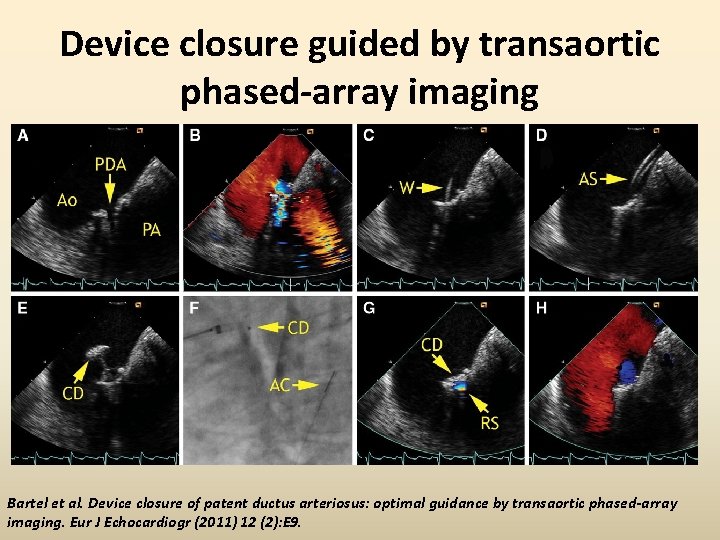

Device closure guided by transaortic phased-array imaging Bartel et al. Device closure of patent ductus arteriosus: optimal guidance by transaortic phased-array imaging. Eur J Echocardiogr (2011) 12 (2): E 9.